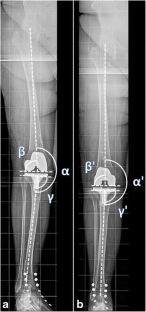

In 100 long leg radiographs coronal femoral and tibial component alignment and hip knee ankle angle (HKA) were measured. Present rotational errors in long leg radiographs were determined by fibular overlap and its impact on alignment parameters calculated.